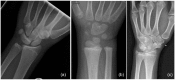

Background: Carpal coalition and metacarpal synostosis are uncommon congenital anomalies of the carpus and hand. Methods: A comprehensive review of the literature was performed to help guide surgical and non-surgical treatment of carpal coalition and metacarpal synostosis. Results: The embryology, epidemiology, medical and surgical management, and associated outcomes are detailed. Conclusions: Most patients with these disorders will likely benefit from conservative measures. Surgery should be considered in patients with pain and limitations in wrist and hand function.